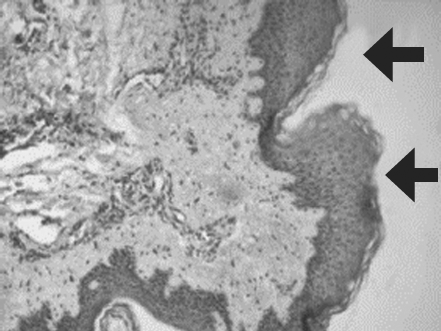

The results of three-year research on the use of allogeneic mesenchymal stem cells of adipose tissue (AMSCs) in the treatment of skin burns of II-III degree are presented. in a complex with wounds dressing of nanofibers chitosan and copolyamide, hyaluronic acid. It was found that with surgical necrectomy, introduction of AMSCs and substitution of defects with natural polymer coatings, the healing time is reduced by 89% (p < 0.05). Isolated administration of MSC reduces the healing period by no more than 5% (p > 0.05). The combined use of wounds dressings of nanofibers chitosan and copo lyamide with MSC accelerates the regeneration process by 26% (p < 0.05), with the introduction of AMSCs accelerating the development of granulation tissue by the fifth day of observation by 83% (p < 0.01). Joint use of wound coverings on the basis of hyaluronic acid with AMSCs is accompanied by an increase in the number of vessels of the microcirculatory bed in the defect area by 185% (p < 0.01). Clinical evaluation of the effectiveness of drugs with stem cells – a gel for topical application and a suspension of MSC LC for injection administration demonstrate their ability to optimize regeneration in the burn zone. Application of gel with AMSCs reduces the duration of epithelialization of border (dermal) burns by 2.2-2.4 times, with the final healing period being reduced by 59% (p < 0.01) and the suppuration frequency by 30% (p < 0.05). The introduction of a suspension of AMSCs into the zone of deep burn increases the frequency of engraftment of autografts, stimulates angiogenesis and proliferation of fibroblasts in the superficial and deep layers of the dermis. In the area of MSC administration, the LC perfusion level and the amplitude of blood flow fluctuation are twice as high as the values in the zones without the introduction of cells.